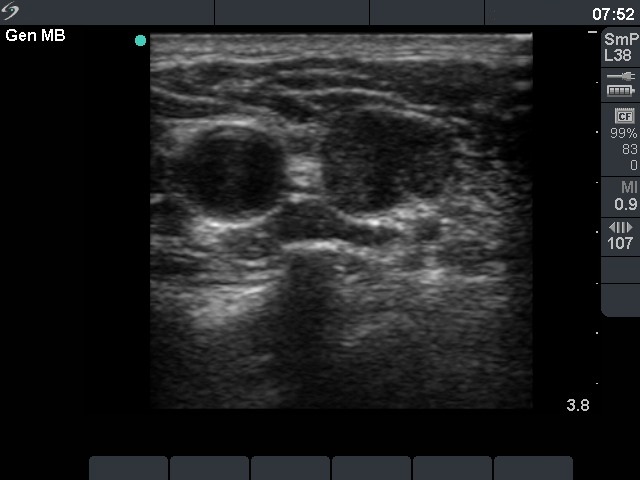

Thyroid cancers - case 209 (ultrasonographic picture 4)

Left side of the neck. The artery is left while an enlarged lymph node is right in the picture. Note that the lymph node is almost round and lacks hilum. The heterogeneous echo pattern is also a suspicious ultrasound characteristic in lymph nodes.